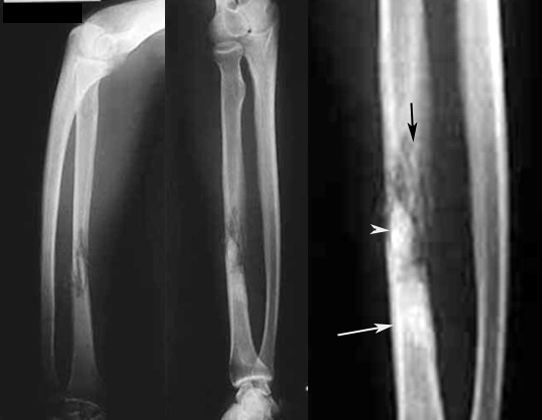

Osteomyelitis

• Black arrow points to bony destruction.

• White arrow points to sequestrum.

• Arrowhead points to area of sclerosis indicating chronicity.